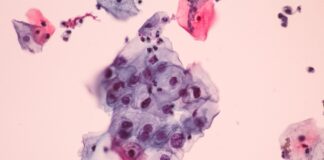

A Common Virus Causes Cancer, but Most Americans Are Clueless About...